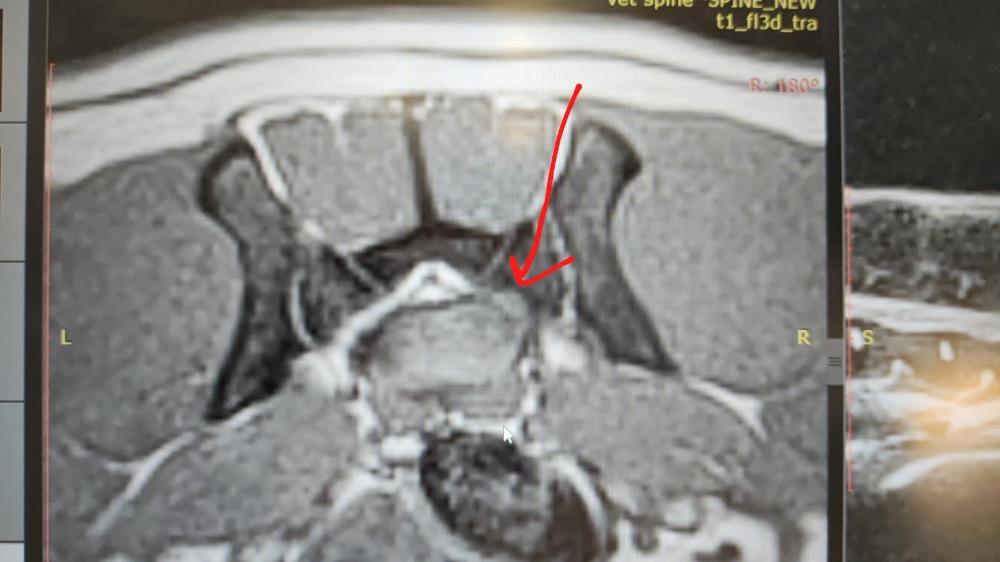

Татьяна_Таймыр Опубликовано 21 июня, 2025 Автор Опубликовано 21 июня, 2025 Всем привет. Нам ответил невролог из Москвы: Брагин Юрий Михайлович. Он посмотрел само МРТ. Сделал заключение, что основания для хирургического вмешательства нет, и все решаем консервативным методом лечения. Мы имеем дело с отеком и сдавление нерва именно отеком! Есть небольшая протрузия, но она пройдет по мнению врача при консервативном лечении. Это значит что принимаем таблетки ( назначили медрол) и проходим тщательную долгую реабилитацию. Смотрим динамику и состояние Таймыра. Цитирую: «Вот здесь зона наибольшей компрессии корешка» «Использовать ноклинги для пальцев и активно заниматься реабилитацией. Следить, чтобы не стирал на пальцах кожу и когти на левой лапке. Сегодня подготовлю заключение по консультации и Вам вышлю.» 19